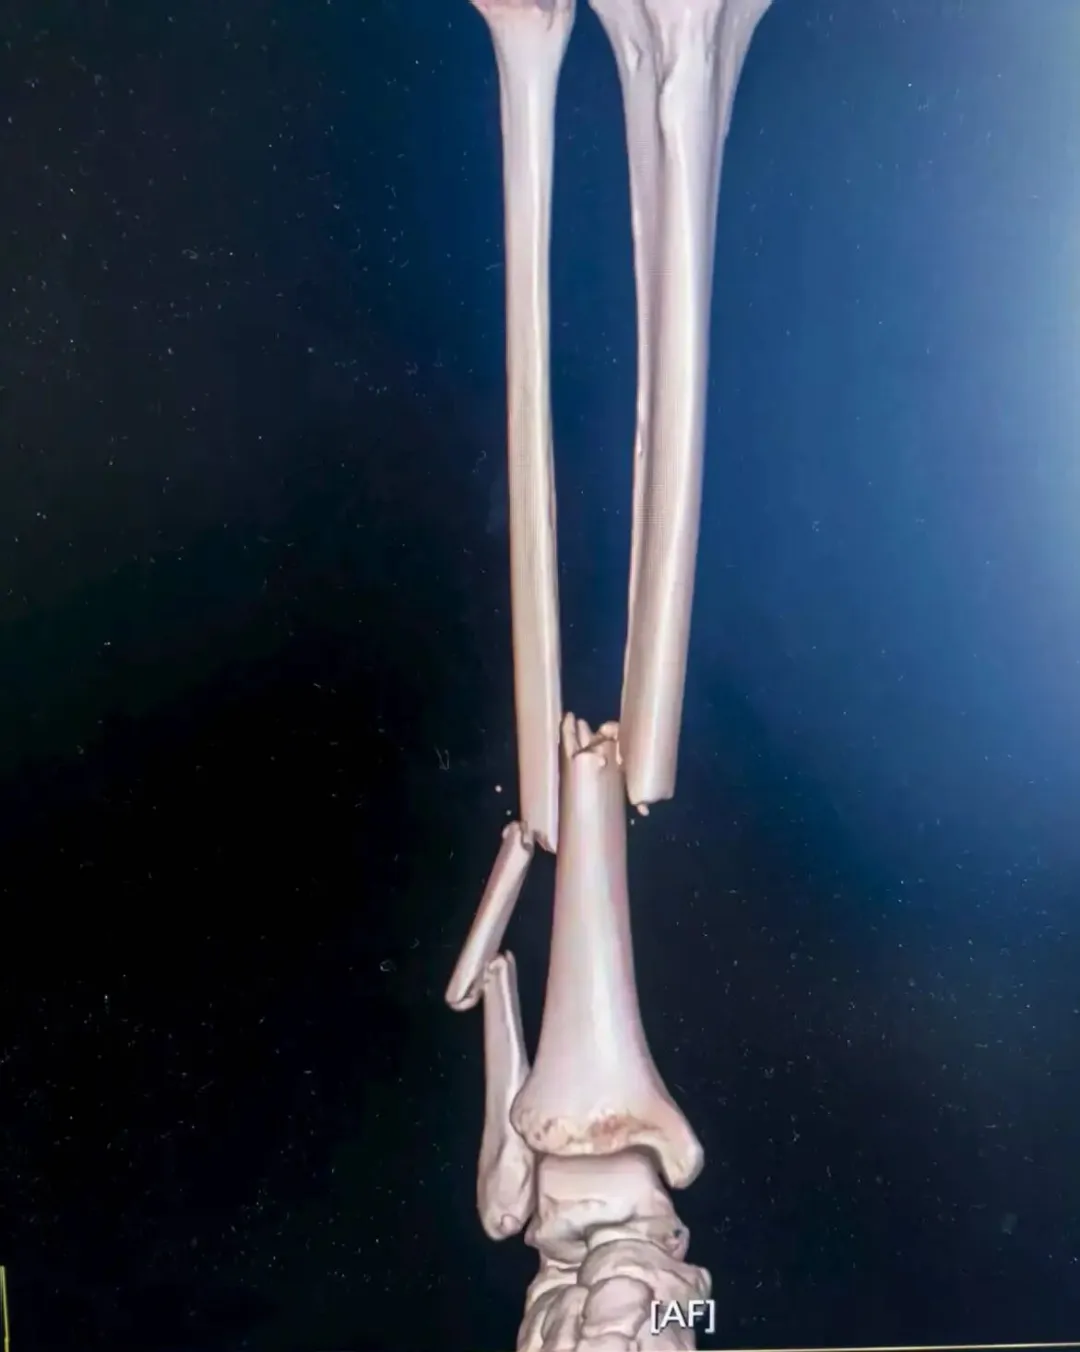

经过诊断,张女士为右侧胫腓骨闭合性骨折,且骨折端移位明显,同时伴有严重软组织肿胀,手足外科孙毅珲主治医师第一时间通过药物与物理治疗控制肿胀、石膏外固定等避免继发性损伤,为后续手术创造安全条件。

考虑到张女士是外地游客,不仅希望骨折能精准复位,还盼着创伤小、恢复快,不耽误后续返程与康复。董伟副主任医师结合影像学资料,综合考虑张女士的身体状况与个人需求,最终确定采用“胫腓骨骨折闭合复位+胫骨髓内钉内固定术+腓骨髓内针内固定术”,全程无需做大切口,通过微创方式实现骨折端精准对位,既能最大程度保护肿胀的软组织,又能显著提升术后恢复速度。